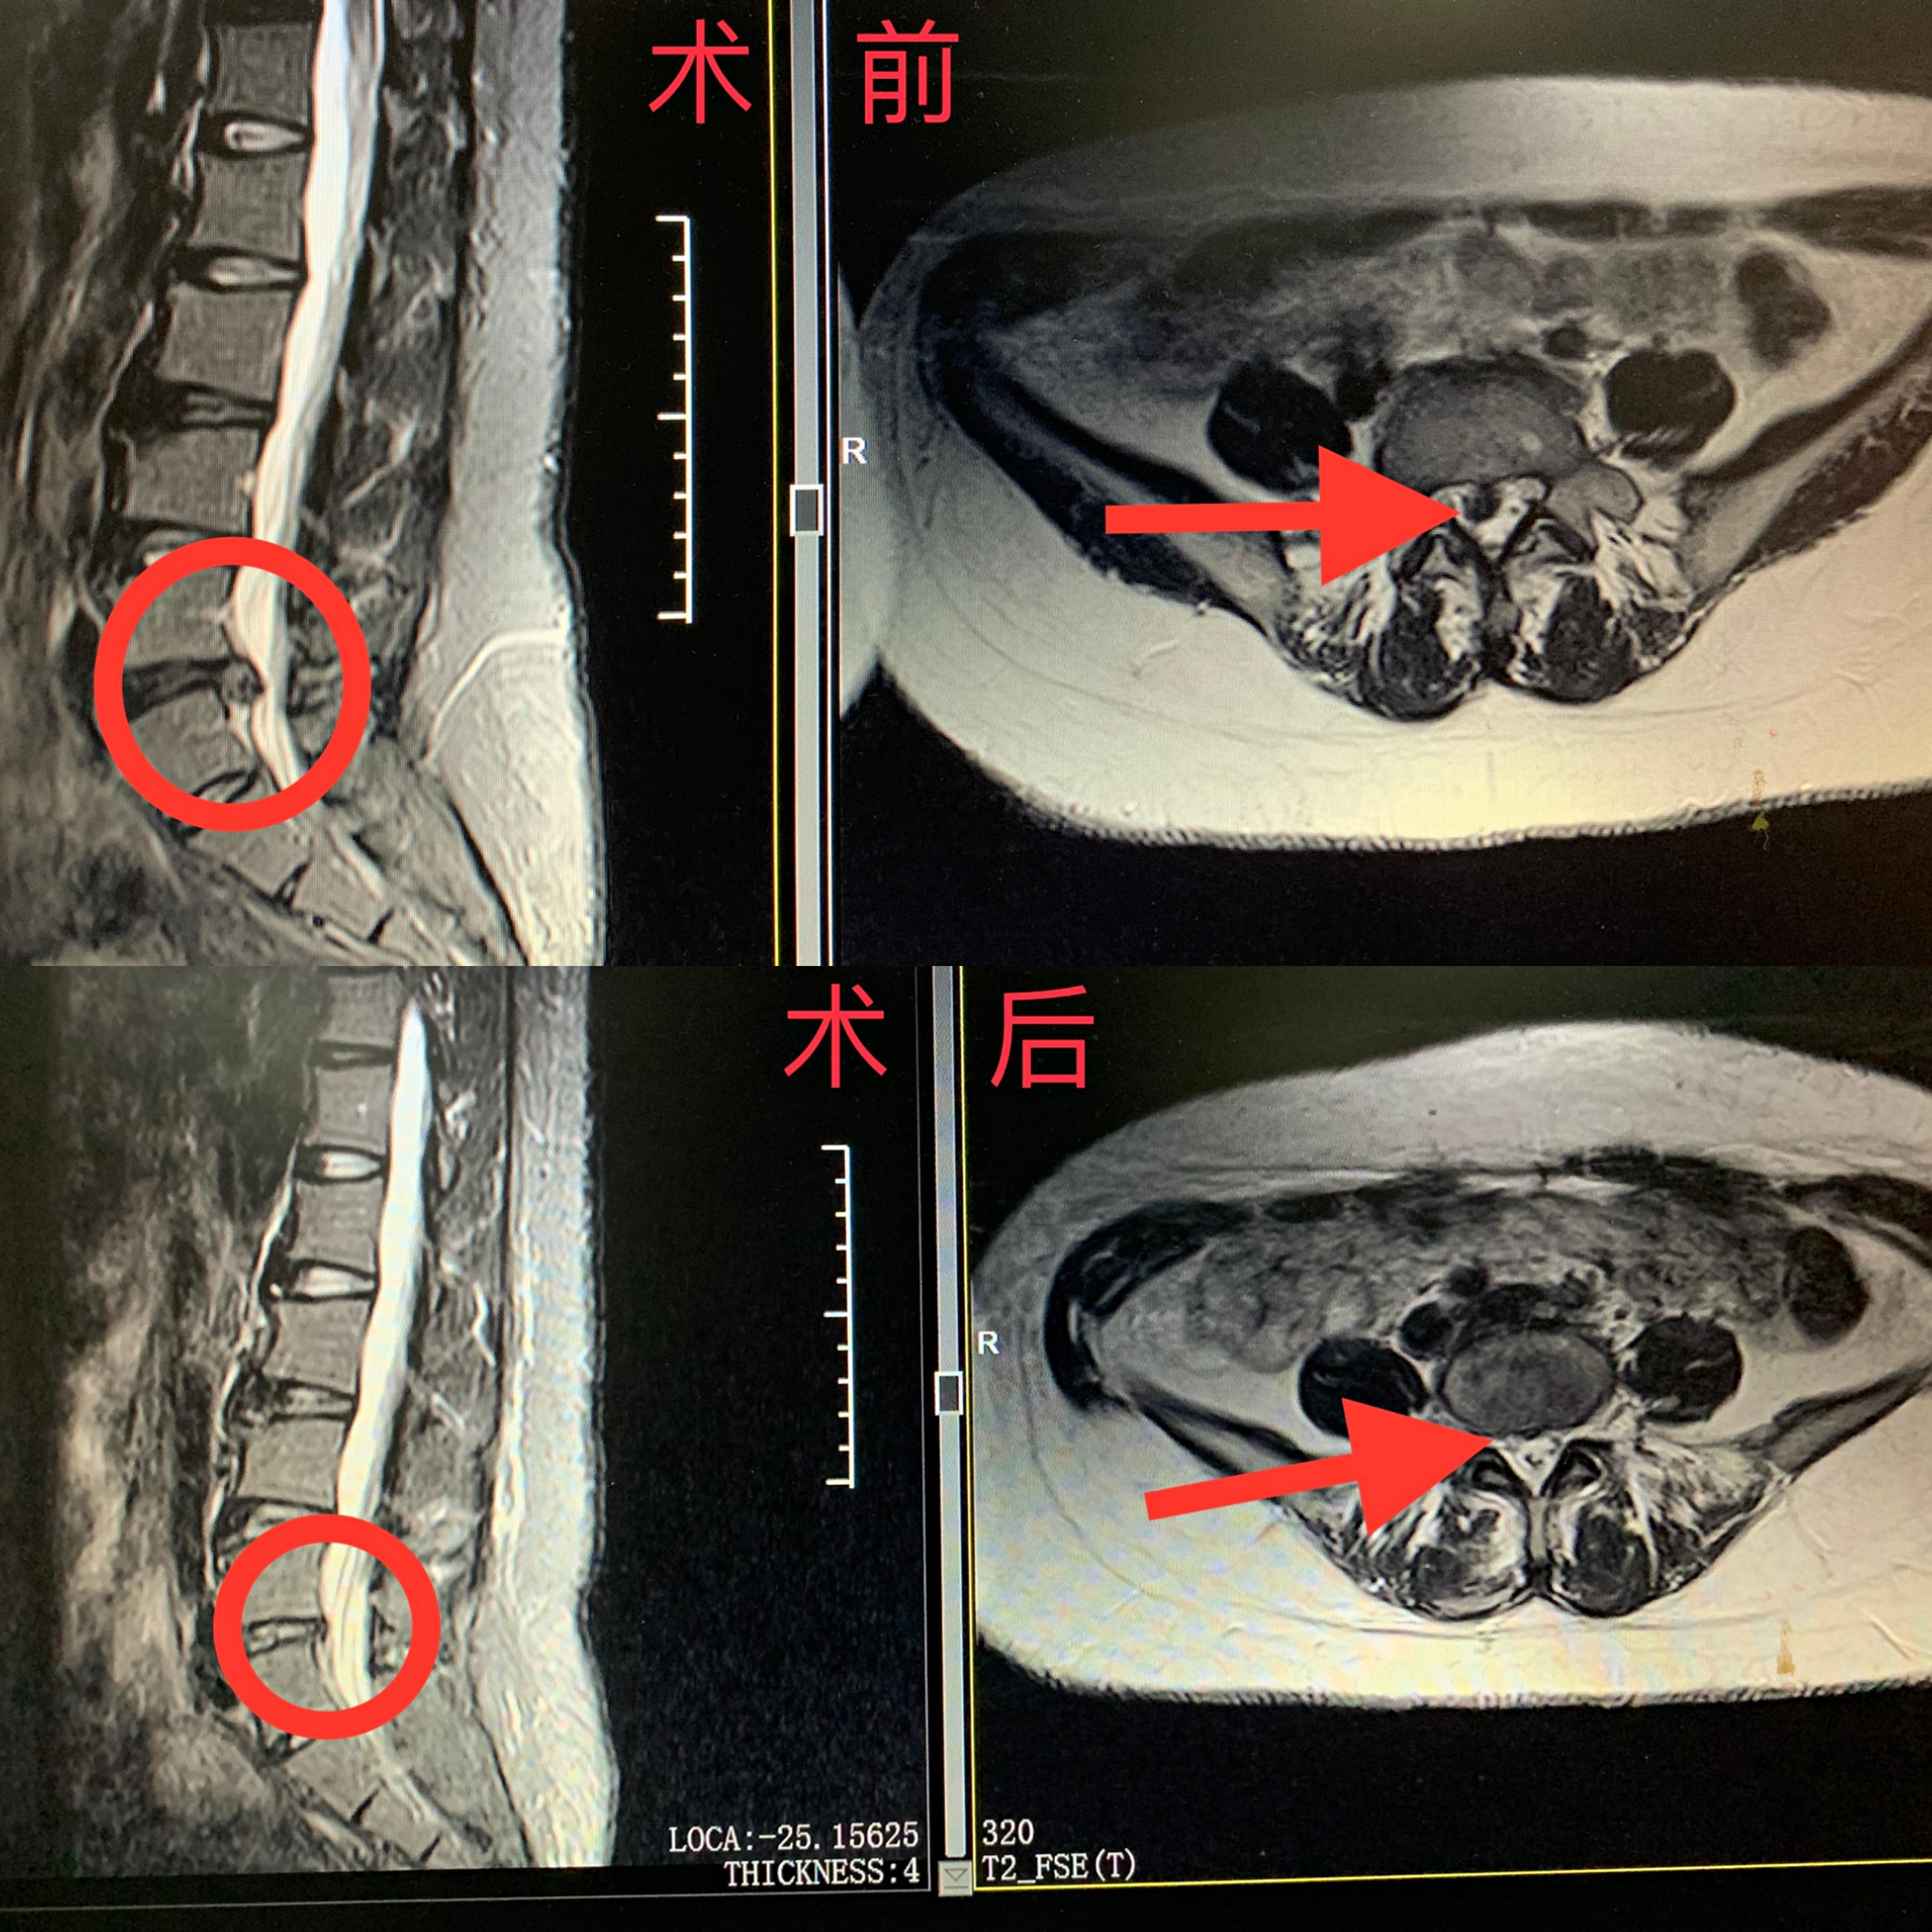

近日,汪先生慕名来到市中医医院骨伤三科就诊,在完善相关检查后,诊断为腰椎间盘突出症。经过科室会诊,考虑到患者为年轻男性,决定以微创治疗为主。科主任刘建国介绍说,患者的椎板间隙相对比较大,加上患者髂棘较高,后者是必然选择。

手术过程非常顺利,巨大且伴有骨化的突出椎间盘被完全摘除,术后患者右臀部右下肢疼痛完全缓解,直腿抬高试验由20度恢复到70度,汪先生感激地握着医生的手说:“我才20岁,之前好害怕年纪轻轻就要瘫在家里,真的特别感谢你们解除了我的心头大患!”